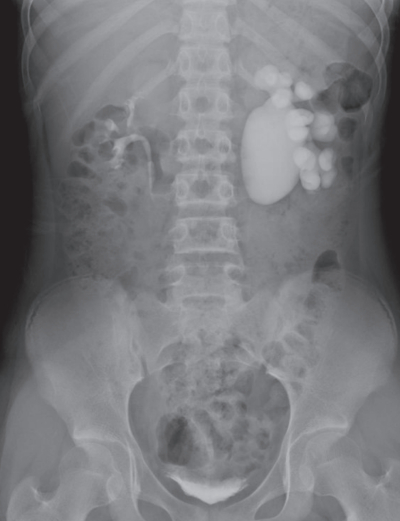

血液所見:赤血球 474 万、Hb 13.0 g/dL、Ht 40 %、白血球 6,500、血小板 28 万。血液生化学所見:総蛋白 6.7 g/dL、アルブミン 4.3 g/dL、総ビリルビン 0.3 mg/dL、AST 14 U/L、ALT 8 U/L、LD 156 U/L(基準 120~245)、尿素窒素 9 mg/dL、クレアチニン 0.5 mg/dL、尿酸3.5 mg/dL、 血 糖 82 mg/dL、Na 144 mEq/L、K 4.0 mEq/L、Cl 108 mEq/L、Ca 8.8 mg/dL。腹部単純 CT で尿路に石灰化陰影や走行異常を認めない。腹部造影 CT 水平断像、造影 CT 後の腹部エックス線写真及び利尿レノグラムを別に示す。